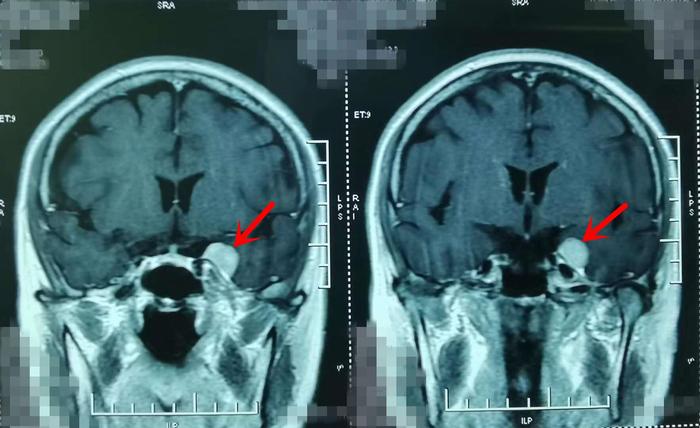

术前影像学资料

“从刘阿姨核磁检查上来看,肿瘤并不算太大,但是位置很特殊,周围多是神经与血管,这给手术增加了难度。不过你们也不要担心,这类手术在我们这里是很常规的手术,你们从银川远道而来,这是对我们最大的信任,我也得让你们放心,让刘阿姨健健康康的回家!”门诊中,张治国教授耐心细致的为刘阿姨和女儿分析着病情。

完善各项术前准备后,刘阿姨被推进了手术室,张治国教授亲自为刘阿姨做手术。肿瘤基底从蝶骨嵴向海绵窦壁、岩骨生长,凭借20多年的从医经验,再加上准确精细的手术操作,张治国教授通过颞下入路手术切除肿瘤后,可以看见动眼神经、颈内动脉、小脑幕保护的很好,同时颞叶脑组织和回流静脉也完好无损,手术非常成功!